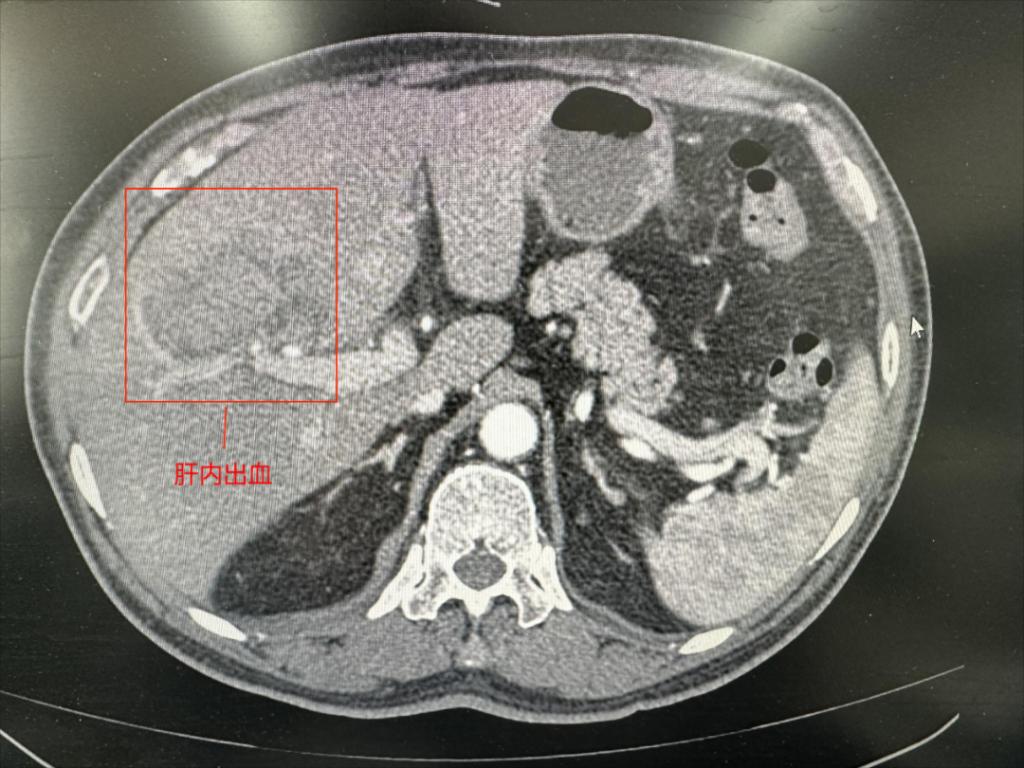

2023年11月2日,64岁的薛先生突发意识丧失,晕倒后伤及右上腹部,由路人拨打120就诊于我院急诊,自述感右上腹剧烈疼痛。立即行CT检查提示:肝右叶挫裂伤、肝内血肿表现。初步诊断为肝脏破裂出血。医院开通紧急救治绿色通道,紧急启动多学科联合会诊。患者系多发伤,病情危重,肝挫裂伤若在全麻下行开腹手术,手术风险极大,即使手术取得成功,也可能会在后期康复过程中面临多种并发症。经我院会诊专家再三讨论,最终决定行介入手术治疗。

肝脏破裂介入治疗无需全麻,仅通过约1毫米的血管穿刺点进行血管内操作,在DSA下寻找出血点,用栓塞材料“堵”住止血点即可,可在短时间内达到快速止血、抢救病人生命的同时,大大减少血液制品的需求。这种新型的微创介入手术既可以及时抢救生命,又可以大大降低手术风险,减少并发症。时间就是生命,在征得患方同意后,介入团队迅速为患者实施手术抢救。近一个小时的手术,精准地将栓塞材料堵住出血点,成功挽救了患者的生命,提高了患者的生存质量,为患者的后续治疗赢得了机会。